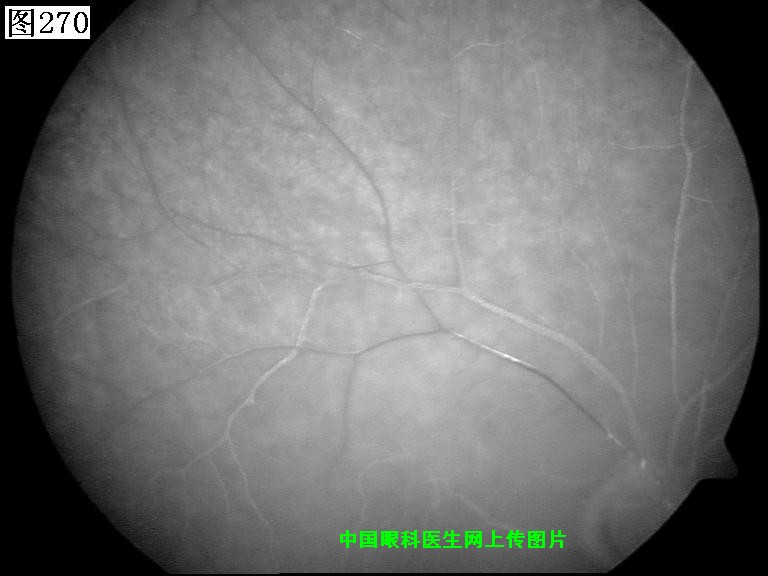

269 270 271 272